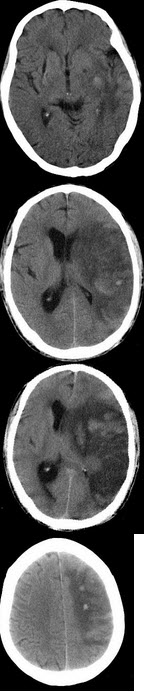

男,58岁,突然出现右侧肢体无力,CT检查如图,最可能的诊断为( )

A:星性细胞瘤

B:胶质母细胞瘤

C:出血性脑梗死

D:转移瘤

E:脑梗死